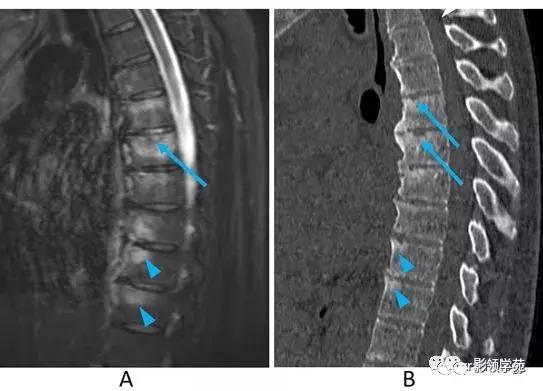

图5:化脓性脊椎炎。男,50多岁。

A:STIR矢状面图像,B:T1WI矢状面图像,C:T2WI矢状面图像。

MRI图像显示L4/5椎间隙变窄和边界不清的骨质破坏(A-C箭)。在STIR(A)和T2WI(C)上骨髓信号呈弥漫性高信号,在T1WI(B)上呈低信号。STIR图像还可以看到相邻椎旁软组织的水肿和/或炎症(箭头)。